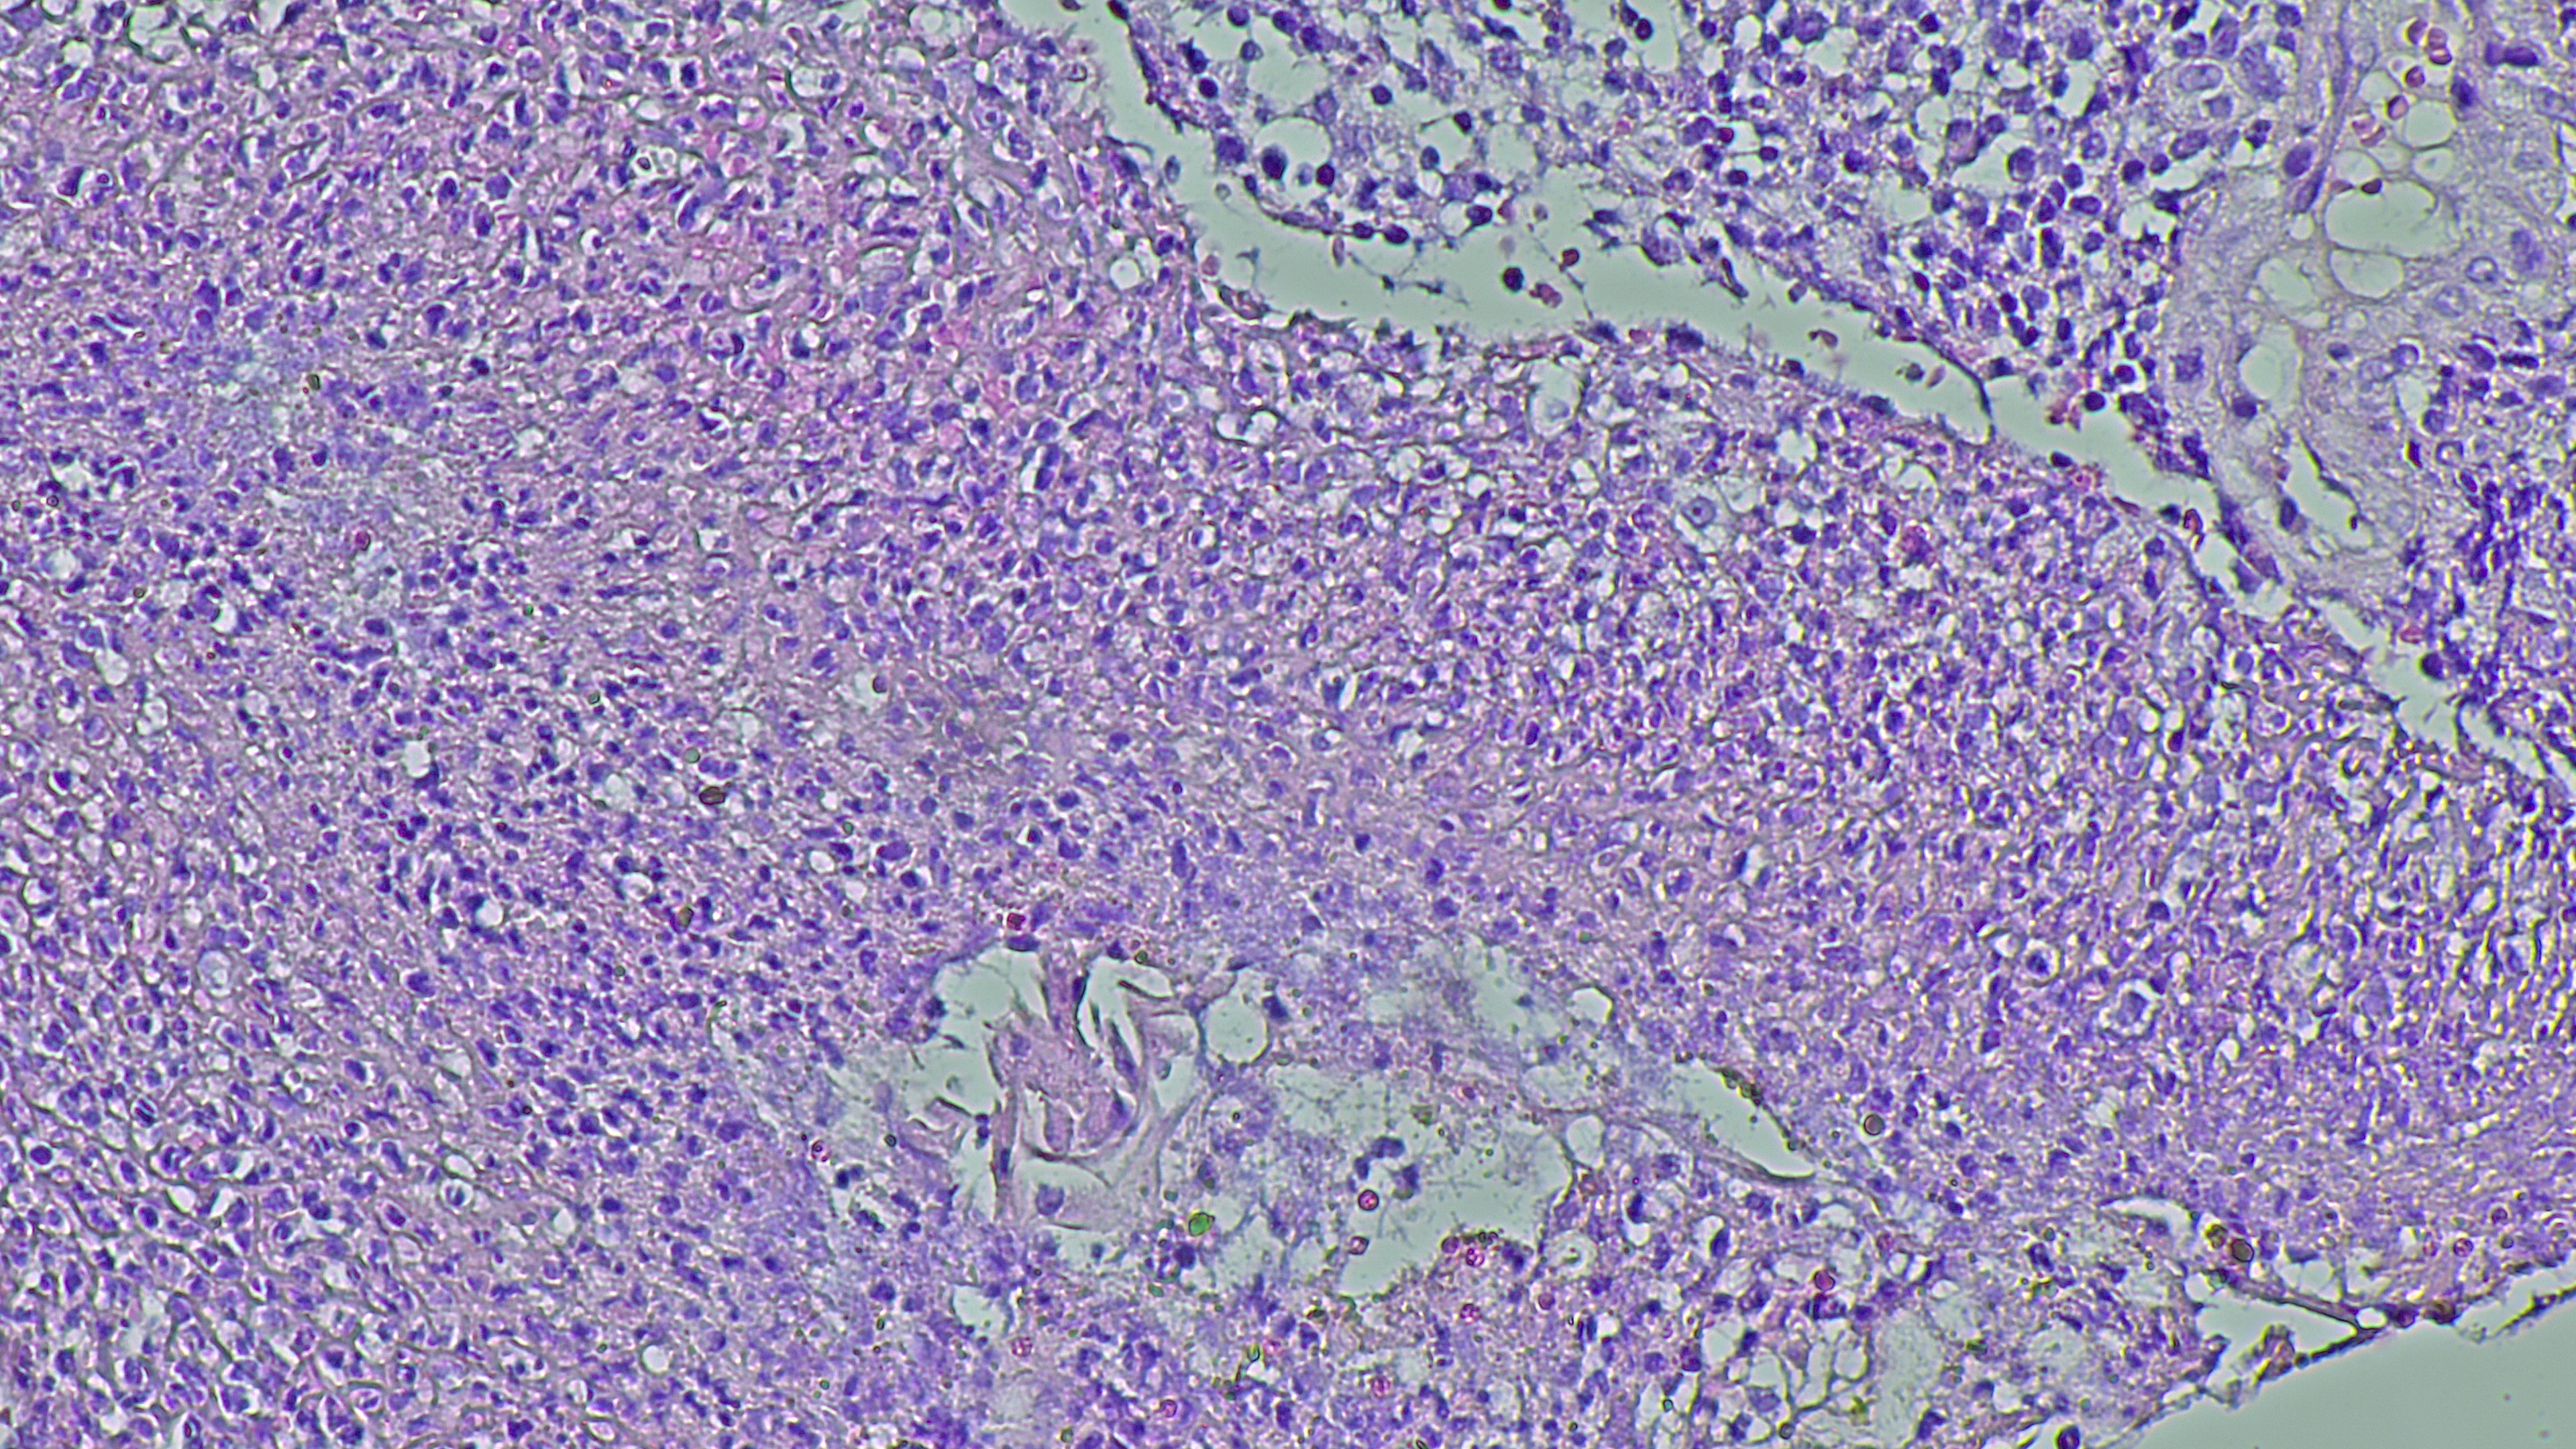

Nowe terapie w hematoonkologii

Hematoonkologia jest dziś jednym z najbardziej dynamicznych obszarów medycyny. W krótkim czasie do praktyki klinicznej weszły terapie, które nie tylko wydłużają życie pacjentów, lecz także realnie zmieniają naturalny przebieg chorób nowotworowych krwi. Ten postęp rodzi jednak nowe pytania: jak finansować innowacyjne technologie, jak organizować leczenie w wyspecjalizowanych ośrodkach i jak pogodzić innowacyjność z ograniczeniami systemu ochrony zdrowia.